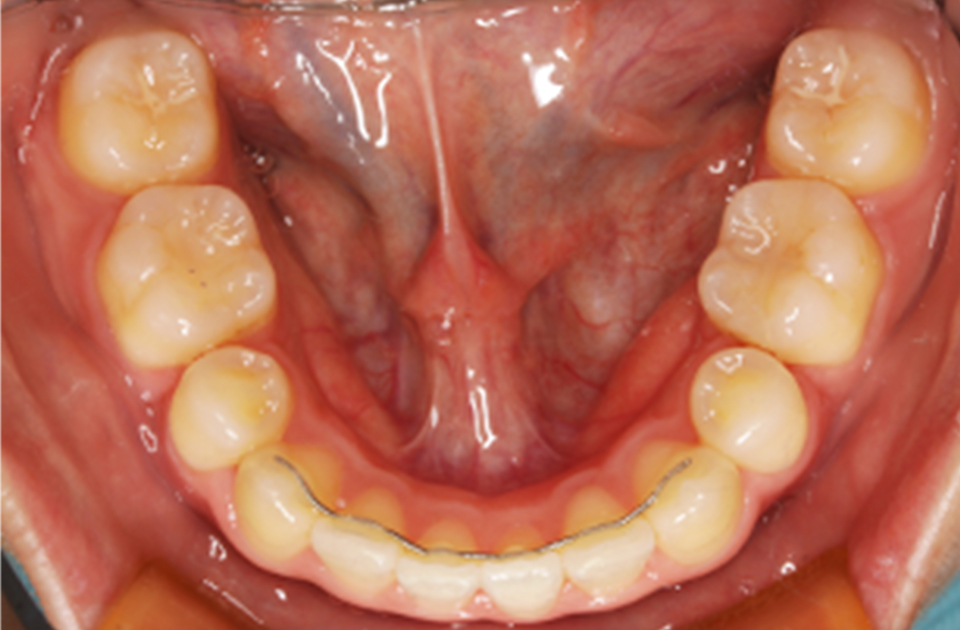

矯正前 下顎

矯正後 下顎